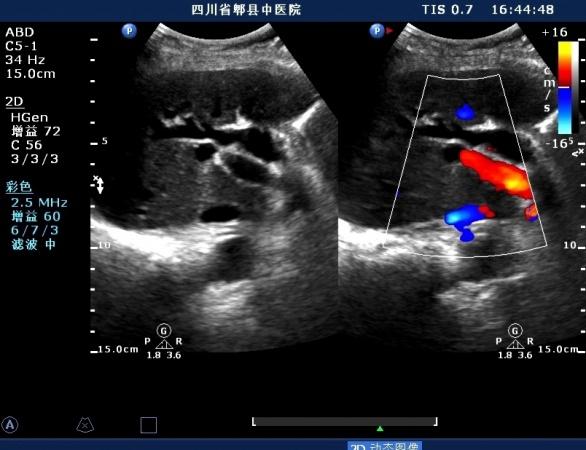

超声如图:胆总管及肝内胆管扩张,呈“平行管征”,胆总管胰腺段可见疏松强回声团堆积,后方可见淡淡声影,左肝外叶胆管内亦可见数个强回声团堆积,后方伴声影。 肝脏及胆总管

胆总管胰腺段结石